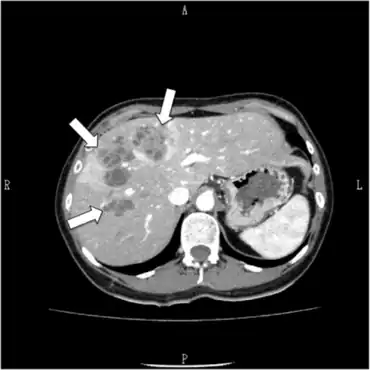

CT findings in an individual with fascioliasis

Most immunodiagnostic tests will detect infection and have a sensitivity above 90% during all stages of the diseases. In addition antibody concentration quickly drops post treatment and no antibodies are present one year after treatment, which makes it a very good diagnostic method.[4] In humans, diagnosis of fasciolosis is usually achieved parasitologically by findings the fluke eggs in stool, and immunologically by ELISA and Western blot. Coprological examinations of stool alone are generally not adequate because infected humans have important clinical presentations long before eggs are found in the stools.

Methods based on antigen detection (circulating in serum or in faeces) are less frequent. In addition, biochemical and haematological examinations of human sera support the exact diagnosis (eosinophilia, elevation of liver enzymes). Ultrasonography and xray of the abdominal cavity, biopsy of liver, and gallbladder punctuate can also be used (ref: US-guided gallbladder aspiration: a new diagnostic method for biliary fascioliasis. A. Kabaalioglu, A. Apaydin, T. Sindel, E. Lüleci. Eur. Radiol. 9, 880±882 (1999) . False fasciolosis (pseudofasciolosis) refers to the presence of eggs in the stool resulting not from an actual infection but from recent ingestion of infected livers containing eggs. This situation (with its potential for misdiagnosis) can be avoided by having the patient follow a liver-free diet several days before a repeat stool examination.[46]